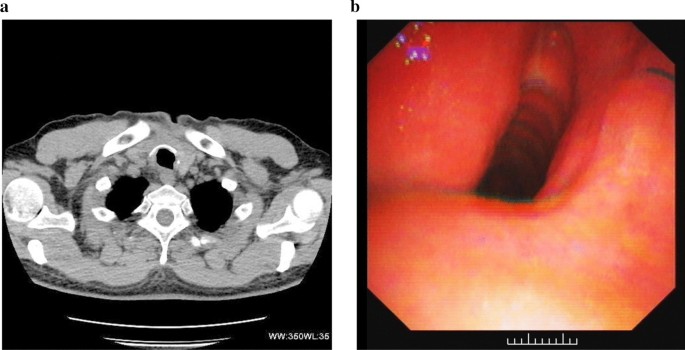

The admission chest radiograph showed a high-density nodule in the trachea at approximately the level of the 7th cervical vertebra, while there was no obvious abnormality found in either lung (Fig. 1a). Chest CT images also revealed a high-density nodule in the trachea at the same level as seen on the chest radiograph. The image showed the nodule inserting into the right thyroid. The foreign body was well-defined, irregular, about 35 mm × 19 mm × 25 mm in size, and measured 1750 HU for its CT attenuation value. The widest space between the tracheal wall and the foreign body was only about 6.5 mm (Fig. 1b, c). Fiberoptic bronchoscopy revealed a black foreign body with an irregular shape in the subglottic trachea. The tracheal lumen was mostly blocked, and granulomatous hyperplasia could be seen at the interface between the foreign body and the tracheal mucosa. However, the fiberoptic bronchoscope failed to pass through the trachea due to its severe stenosis (Fig. 1d).

Radiological examinations and fiberoptic bronchoscopy were performed on a 49-year-old man with a tracheal coal foreign body prior to surgery. a Chest radiograph shows a high-density nodule (arrows) in the trachea about the level of the 7th cervical vertebra. b, c Chest axial and coronal CT images also reveal this high-density nodule (arrows) inserted from the trachea into the right thyroid at the same level as seen on the chest radiograph. d Fiberoptic bronchoscopy reveals a black foreign body in the subglottic trachea. The tracheal lumen was mostly blocked and the fiberoptic bronchoscopy failed to pass through the trachea due to its severe stenosis

In follow-up treatment one month after the operation, the patient underwent a chest CT and fiberoptic bronchoscopy. No tracheal abnormality was found on the CT images and the fiberoptic bronchoscopy only showed a slight tracheal stenosis at the original surgical site (Fig. 2a, b). In the subsequent 3-month follow-up period, the patient reported no acute clinical episodes, and no general problems in his work or ordinary activities.

The patient again underwent CT examination and fiberoptic bronchoscopy one month after the operation. a An axial CT image shows that the tracheal cavity was regular after the original foreign body was removed. b Fiberoptic bronchoscopy reveals that the tracheal cavity was slightly narrow, but the tracheal mucosa was normal